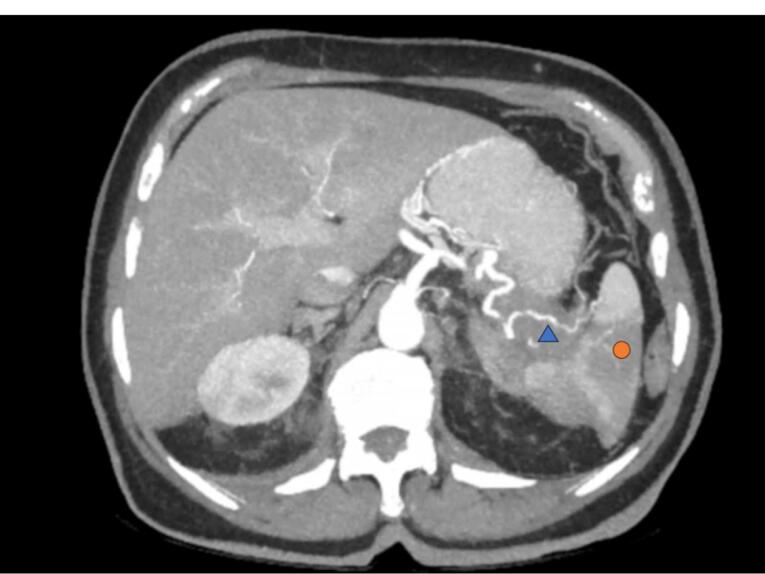

胰腺腺癌是最具侵袭性的肿瘤之一。确诊时通常已是局部晚期或转移性疾病,存活期不到一年。最常见的转移部位是肝脏、腹膜和肺部。骨骼或大脑等其他器官的受累程度较轻。胰腺腺癌的皮肤受累极为罕见,自 1960 年以来,文献报道的病例不到 150 例。大多数皮肤受累病例的病变位于脐周,被称为 "玛丽-约瑟夫修女结"。头皮转移非常罕见,确诊时已是晚期,预后很差。进行全面的体格检查和全面的病史询问非常重要,可为诊断检查的申请提供指导。一旦确诊为胰腺腺癌,就有必要进行全面评估,包括不同的医疗专家、护士、心理学家和社会工作者等。在许多情况下,支持性护理是治疗的主要手段。

Pancreatic adenocarcinoma is one of the most aggressive tumors. Its diagnosis is usually made in locally advanced or metastatic disease and survival is less than one year. The most frequent sites of metastatic involvement are the liver, peritoneum and lungs. Other organs such as the bones or the brain may be affected to a lesser extent. Cutaneous involvement of pancreatic adenocarcinoma is extremely rare with less than 150 cases reported in the literature since 1960. Most cases with cutaneous involvement involve the periumbilical region, in a lesion known as "Sister Mary Joseph's Node". Scalp metastases are very rare and their diagnosis suggests advanced disease and the prognosis will be dismal. It is very important to perform a complete physical examination and a global anamnesis to guide the request for diagnostic tests. Once the diagnosis of pancreatic adenocarcinoma has been made, a global assessment will be necessary, involving different medical specialists, nurses, psychologists and social workers among others. In many cases, supportive care is the mainstay of treatment.